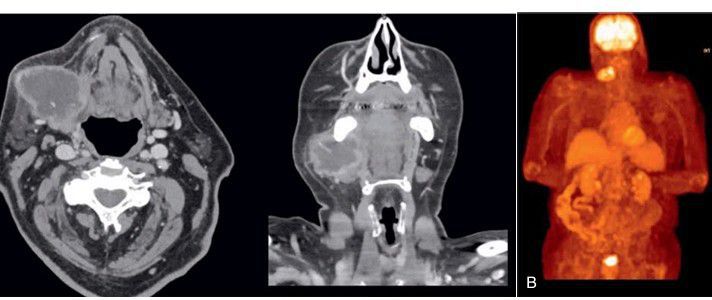

(A) Computed tomography scan of malignant neoplasm of right submandibular gland. (B) Corresponding fluorodeoxyglucose positron emission tomography scan showing the same malignant neoplasm of right submandibular gland